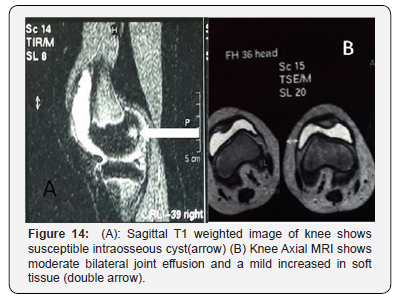

Laboratory tests revealed normal ranges of CBC, ESR, CRP, Albumin, Creatinine, Urea, electrolytes. Anti-CCP, RF, ANAwere all negative. Cardiac ultrasound showed no effusion. Knee ultrasound showed bilateral moderate effusion. Plain radiograph of both hands showed flexion at the 4th and 5th distal interphalangeal (DIP) joints of the right hand (Figure 11). Knees X-ray (Figure 12) and pelvis anterior-posterior radiograph (Figure 13) showed similar findings to her younger sister. Knees MRI revealed a mild increased in soft tissue, moderate bilateral joint effusion and intraosseous filled-fluid herniation (Figure 14). Hip MRI showed moderate effusion and susceptible intraosseous cysts without erosions (Figure 15). She was discharged along with acetaminophen (15 mg/k) with the possibility of surgery if severe symptoms have developed..

Radiological appearances confirm the diagnosis of CACP. Knees X-ray showed osteopenia, bilateral effusion, swelling of soft tissues, joint space widening, and epiphyseal widening of both knees. Knee MRI image of the older sister, patient 2, showed intraosseous cysts inside the bone, without bone erosion [12].